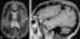

Perisylvian syndrome is a rare neurological disease characterized by damage to the sylvian fissure (lateral sulcus), an area in the brain involved in language and speech. The main symptoms are difficulty chewing and swallowing, low muscle tone in the face and tongue, speech and language development disorders, and epilepsy. [Source: Wikipedia ]